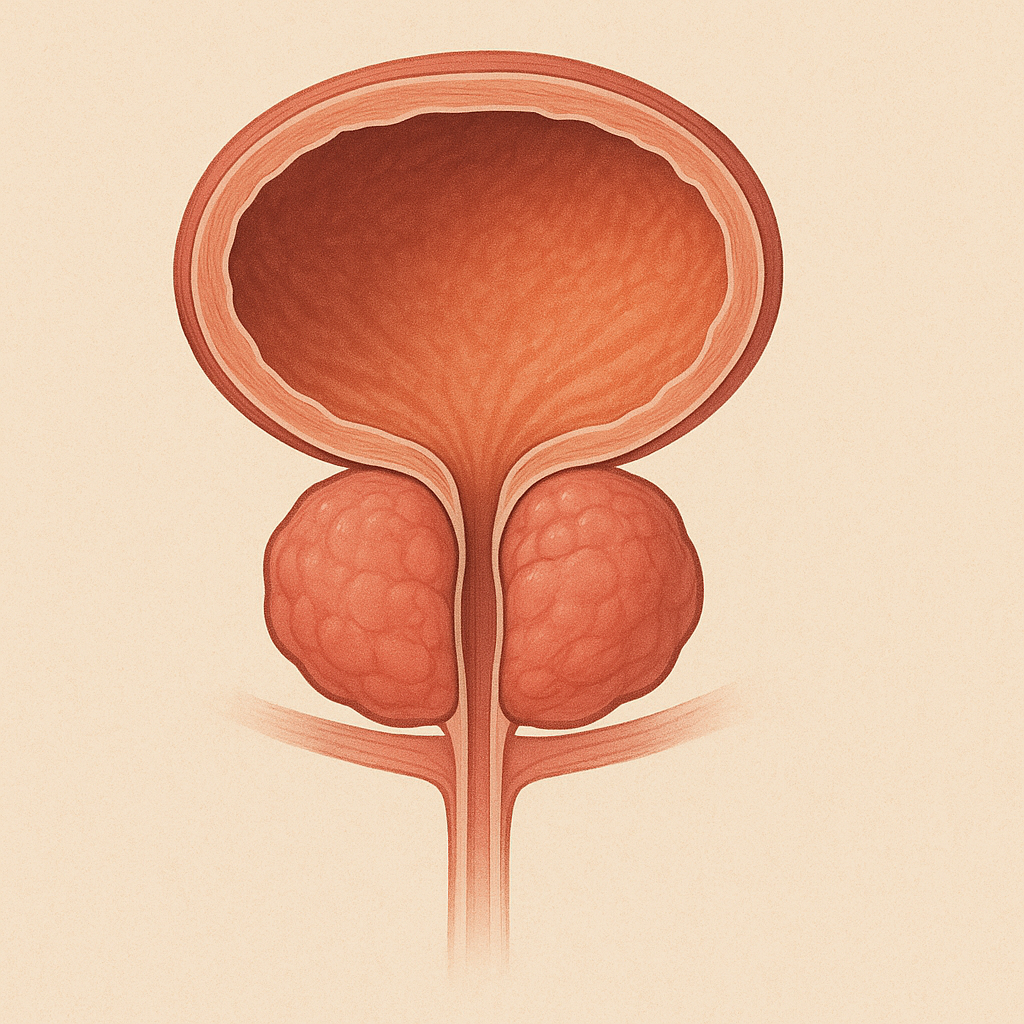

# Renal Problems